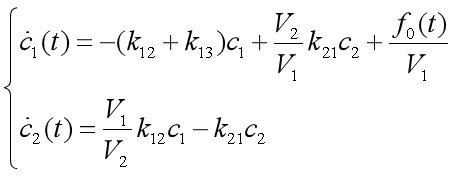

【4.3】

模型【4.3】是线性常系数非齐次微分方程,其解由对应齐次的通解加上这个方程的特解,要求特解,就要知道f0(t)的表达式,下面分几种情况来讨论。

1、快速静脉注射

这种注射可以简化为在t=0瞬时将剂量D0的药物注射输入心脏,血液浓度立即上升为D0/V1,于是初始条件变为 【4.4】

【4.4】

方程组【4.3】在【4.4】条件下的特解为 【4.5】

【4.5】